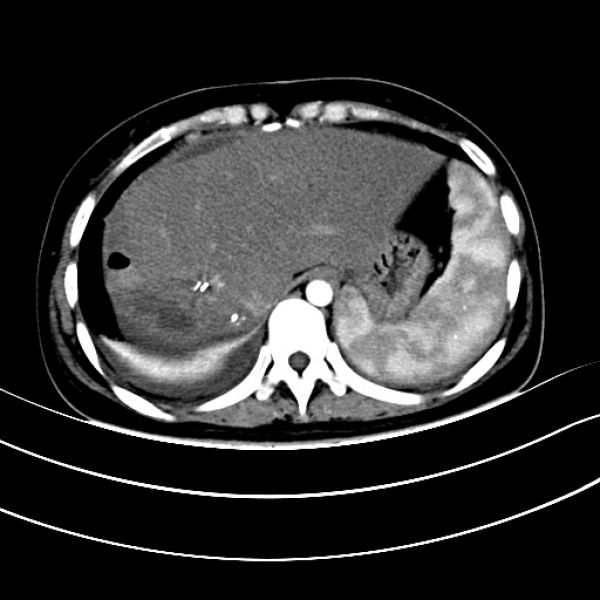

患者转入ICU治疗3天病情稳定后转湘雅医院继续治疗,并再次行肝创面压迫止血棉垫取出术,经积极治疗,患者恢复良好。治疗过程中两次行彩超引导下肝脓肿穿刺引流术,术后病情平稳,恢复出院。患者出院后,因肝脓肿反复住院数次进行脓肿冲洗引流,给患者生理和心理带来了很大影响。8月10患者以“肝脓肿穿刺引流术后3月余”来肝胆一科住院复查治疗,完善肝胆脾CT检查后发现,患者右肝脓肿仍然明显。王文儿主任组织肝胆一科医师进行科内讨论研究指出,通过仔细研究CT片及结合分析患者抢救治疗经过后认为要根治性解决患者目前病灶,必须行右半肝切除。经过与患者家属沟通,仔细说明患者目前病灶情况及治疗方案的利弊之后,家属充分了解并同意手术方案。经过充分术前准备后,于8月14日在全面插管下行右半肝切除+右隔下脓肿清除引流术,术后经积极治疗,患者顺利康复出院。

术后复查CT图像